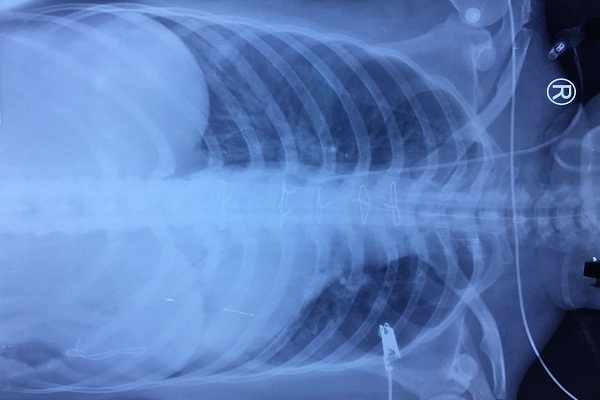

Kết quả chụp X-quang bệnh nhân sau phẫu thuật.